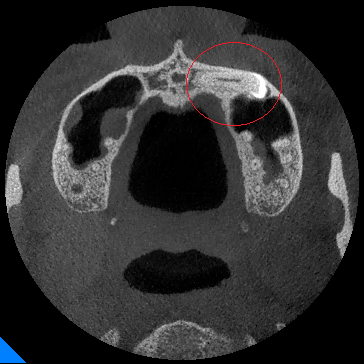

【口腔颌面锥形束CT(CBCT)】

◆埋伏牙

◆牙瘤

◆由囊肿引起的骨质破坏